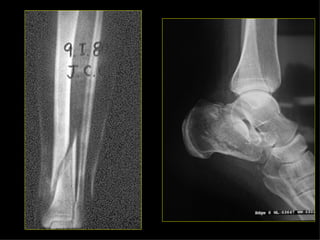

Estudio radiológico Ninguna zona de sospecha de fractura debe tener menos de dos proyecciones con 90º entre sí. En los huesos largos (pareja en extremidades), se deben incluir ambos en su totalidad. En fracturas de extremidades son a veces necesarias proyecciones del lado normal (niños).

Estudio radiológico El mecanismo de dolor referido puede equivocar en cuanto a la situación de la fractura, de importancia en lesiones de cadera y rodilla. Las proyecciones tangenciales son importantes en algunos huesos (planos). Deben incluirse las articulaciones más próximas a la fractura. En fracturas articulares, el estudio deberá incluir radiografías en AP, L, y ambas oblicuas, para detectar posibles fracturas verticales que pueden afectar a la superficie articular.

Estudio radiológico Ningunazona de sospecha de fractura debe tener menos de dos proyecciones con 90º entre sí. En los huesos largos (pareja en extremidades), se deben incluir ambos en su totalidad. En fracturas de extremidades son a veces necesarias proyecciones del lado normal (niños).

Estudio radiológico Elmecanismo de dolor referido puede equivocar en cuanto a la situación de la fractura, de importancia en lesiones de cadera y rodilla. Las proyecciones tangenciales son importantes en algunos huesos (planos). Deben incluirse las articulaciones más próximas a la fractura. En fracturas articulares, el estudio deberá incluir radiografías en AP, L, y ambas oblicuas, para detectar posibles fracturas verticales que pueden afectar a la superficie articular.